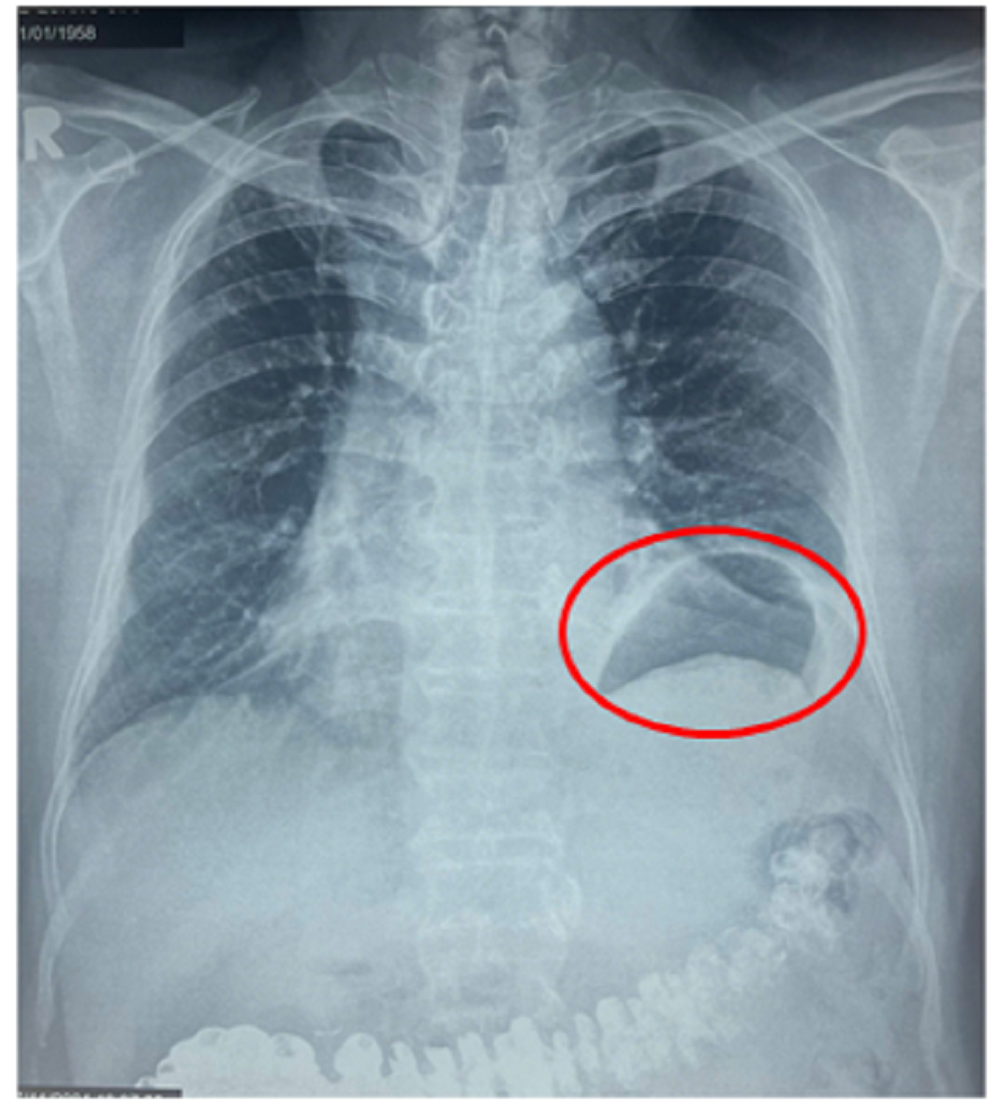

Ông G. cho biết, cách nhập viện khoảng 3 tháng ông thường hay khó thở, thở hụt hơi khi gắng sức, khi vận động hay đi lên cầu thang. Tình trạng này khiến ông không thể vận động thể lực mạnh hay đi bộ tập thể dục với cường độ như trước. Trong đợt khám sức khỏe định kỳ, một bác sĩ khi xem phim X-quang ngực thẳng của ông thì phát hiện vùng phổi bên trái có bất thường và khuyên ông đến Bệnh viện Bình Dân để khám chuyên khoa lồng ngực. Tại Bệnh viện Bình Dân, sau khi thăm khám lâm sàng và xem kết quả chụp X-quang ngực và MSCT-scan ngực, các bác sĩ chẩn đoán ông bị nhão hoành trái với hình ảnh vòm hoành trái nhô cao bất thường. Tình trạng này làm giảm thể tích lồng ngực trái, đây chính là nguyên nhân khiến ông bị khó thở khi gắng sức nhiều tháng nay mà ông không rõ nguyên nhân.

Vòm hoành trái cao bất thường do nhão cơ hoành trái làm giảm thể tích lồng ngực trái gây khó thở gắng sức cho bệnh nhân